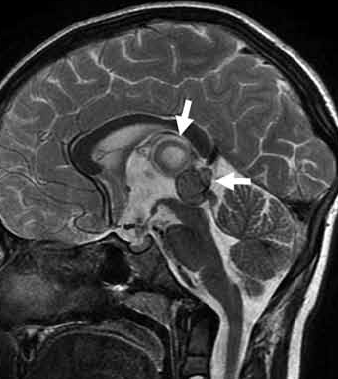

• 松果体区胶质母细胞瘤案例解读一则

松果体区胶质母细胞瘤案例解读一则

2021-01-25 17:33:23

多形性胶质母细胞瘤(GBM)很少在松果体区发现。本文介绍了一个松果体区原发性胶质母细胞瘤(GBM)的病例,讨论了临床过程、影像学表现和治疗方法。根...